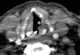

Aorticopulmonary paraganglioma